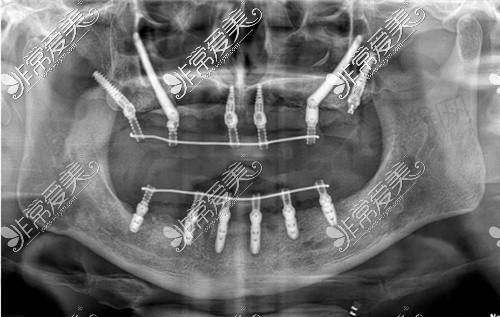

1. 数字化精细种植牙:采用德国卡瓦CBCT三维扫描定位,搭配3D导板实现误差<0.1mm精细种植,支持即刻负重(单颗/多颗缺失当天戴牙)、All-on-4半口/全口种植(24小时修复咬合)及骨量不足病例(骨增量、上颌窦提升、穿颧种植);

1. 精细度提升:采用德国卡瓦CBCT设备,可获取牙槽骨密度、神经管走向等三维数据,结合3D导板引导种植体植入角度、深度,定位误差控制在0.1mm以内,避免损伤神经与上颌窦;

3. 适应症广泛:针对全口牙槽骨萎缩患者,创新应用“穿颧种植技术”,无需植骨即可实现全口修复;半口缺失患者采用All-on-4技术,仅需4颗植体即可修复12-14颗牙齿功能,费用较传统种植节省40%;